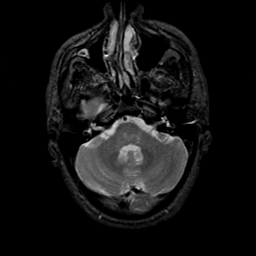

MR Study #9, April 14, 1991 -- Slice #11

[Home][Help][Clinical][Tour 1][Tour 2] Slice 11